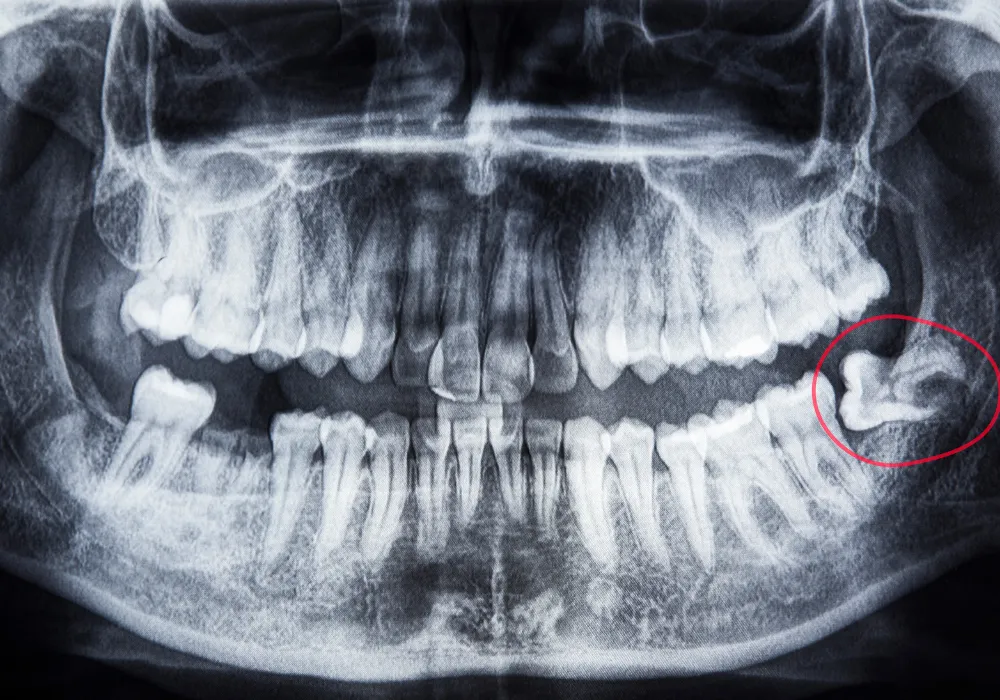

Na to vprašanje lahko odgovori le zobozdravnik. Rentgenski posnetki bodo pokazali, ali so se razvili, kako rastejo in ali je dovolj prostora zanje.